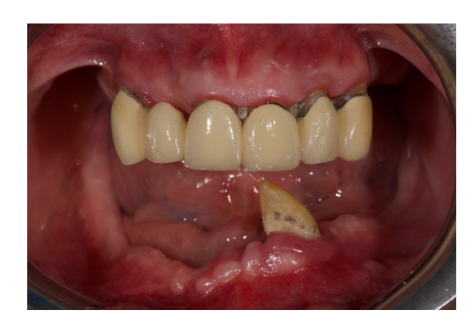

Ниже представлен объяснительный клинический случай. 62-летняя женщина обратилась за вторым мнением из-за существующих съемных частичных протезов, закрепленных на оставшихся естественных элементах, которые были установлены несколько месяцев назад. При клиническом и рентгенологическом обследовании пациентка предъявила основные жалобы на подвижность зубов, кровоточивость десен, боль, дискомфорт, плохую функцию и неэстетичный внешний вид (Рисунки 1 и 2).

Окончательным решением стало переделка обеих реабилитаций. По экономическим причинам пациент вернулся к предыдущему стоматологу с просьбой решить все проблемы. Однако, спустя шесть лет, пациент снова обратился с просьбой решить её жалобы, так как они не были рассмотрены. Предварительные клинические и радиологические анализы показали безнадежное остаточное зубное состояние, характеризующееся тяжелым хроническим периодонтитом, подвижностью, кровоточивостью десен и болью в остаточных верхних зубах, а также одиночным клыком в нижней челюсти. Эстетика и функция также были серьезно нарушены, так как пациент не носил съемные частичные протезы в течение многих лет.